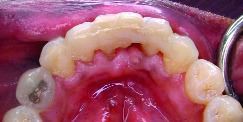

FIGURE 21B